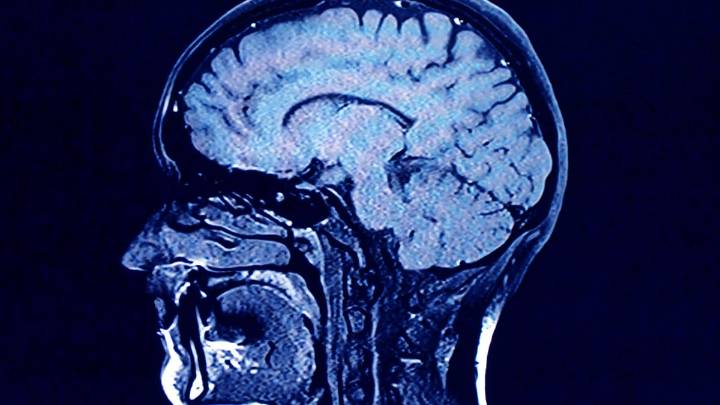

As we age, the human brain rewires itself.

The process happens in distinct phases, or “epochs,” according to new research, as the structure of our neural networks changes and our brains reconfigure how we think and process information.

For the first time, scientists say they’ve identified four distinct turning points between those phases in an average brain: at ages 9, 32, 66 and 83. During each epoch between those years, our brains show markedly different characteristics in brain architecture, they say.

The findings, published Tuesday in the journal Nature Communications , suggest that human cognition does not simply increase with age until a peak, then decline. In fact, the phase from ages 9 to 32 is the only